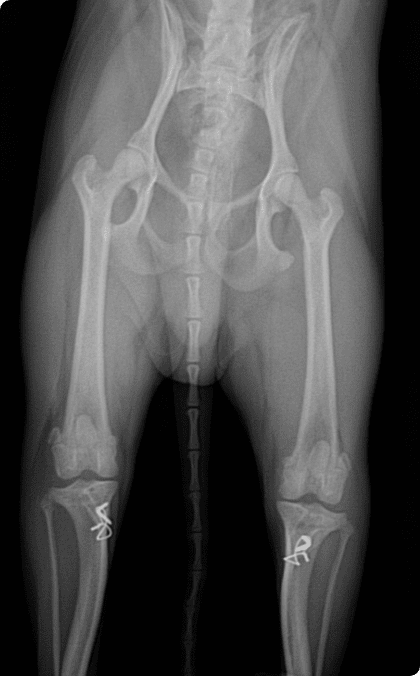

대퇴골 도르래 고랑에서 슬개골이 이탈되는 질환으로

소형견에서 가장 흔히 발생하는 관절 질환.

수술적 교정이 이루어지지 않으면

관절염 악화, 십자인대 파열, 골 변형으로 이어질 수 있음.